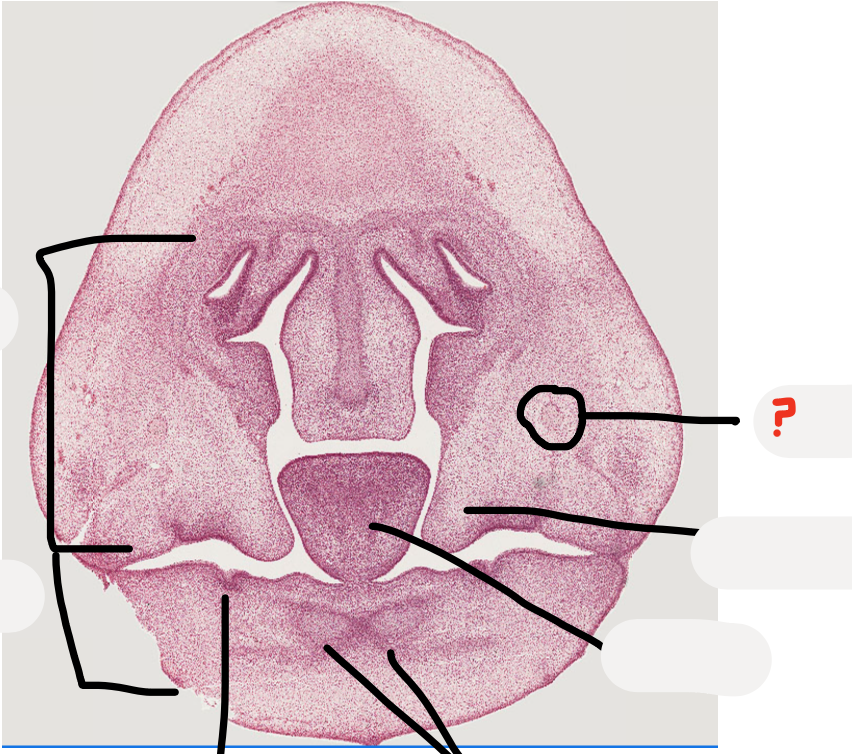

what process is this?

mandibular process

predict what age the embryo is, why?

A

Week 7 as palatal shelves down lateral tongue and tongue takes up most of the space

Week 6 is when see the first evidence of tooth development